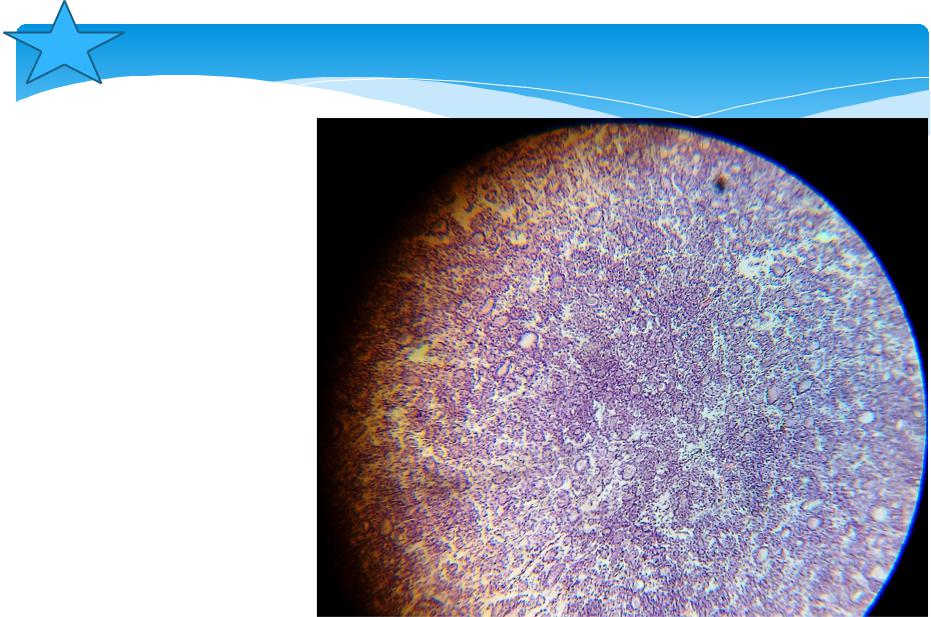

Бактериальная деструкция легких у детей презентация - 88 фото